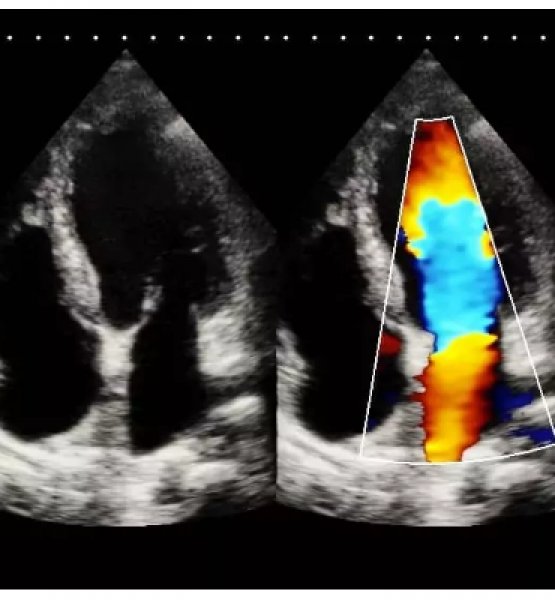

Sonos 12 là hệ thống siêu âm 3D/4D hiện đại bậc nhất với chất lượng hình ảnh hoàn hảo, bao gồm cả hình ảnh 2D.

Đây là giải pháp tốt nhất cho siêu âm các cơ quan nhỏ (vú, tuyến giáp, tinh hoàn), thai nhi & thai phụ, tim (người lớn, trẻ em), Cơ – xương (thông thường & bề ngoài), mạch máu ngoại vi, thực quản, trực tràng, âm đạo & tiết niệu.